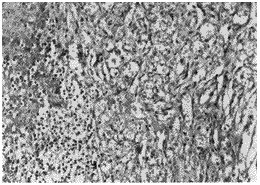

图1 扁桃体结构破坏,由血管瘤样结构取代HE×200

图2 扁桃体肿瘤 瘤组织由毛细血管腔及间质梭形细胞组成HE×200

图3 皮肤肿瘤 血管瘤样结构伴表皮下少量小圆细胞浸润HE×200

图4 皮肤肿瘤 肿瘤深部见典型Kaposi肉瘤结构HE×200

Kaposi肉瘤是由血管内皮细胞增生分化,或由原始幼稚间叶细胞向血管内皮细胞分化所形成的。不同的细胞分化程度和时期,Kaposi肉瘤的组织学表现亦各有差异,本组4例患者的主要组织学改变为血管样结构和梭形细胞增生,其它有淋巴管扩张,梭形细胞或巨噬细胞内嗜酸性透明小球形成,淋巴细胞、浆细胞和巨噬细胞浸润,红细胞漏出,含铁血黄素沉积。病理上需与草莓状血管瘤、血管肉瘤及恶性淋巴瘤等相鉴别[9]。

Kaposi肉瘤的发生时间分别为移植术后3、7、14及21个月,平均11.3个月。首发症状2例为咽喉痛、咽部异物感伴吞咽困难;另2例为双下肢多发对称性紫红色斑丘疹并下肢水肿、腹股沟淋巴结肿大。确诊方法:2例经扁桃体切除病理检查确诊(图1,2)另2例经下肢皮疹和淋巴结活检而确诊(图3,4)。血HIV抗体(-),CMV抗体(-)。